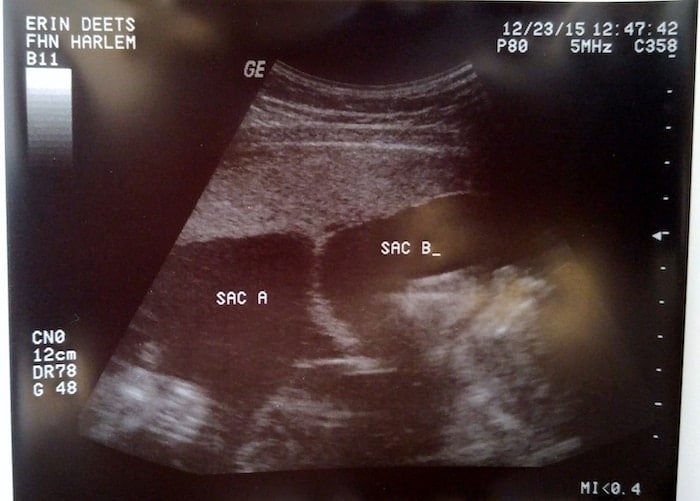

Ultrasound Photos at 21 Weeks Pregnant With Twins